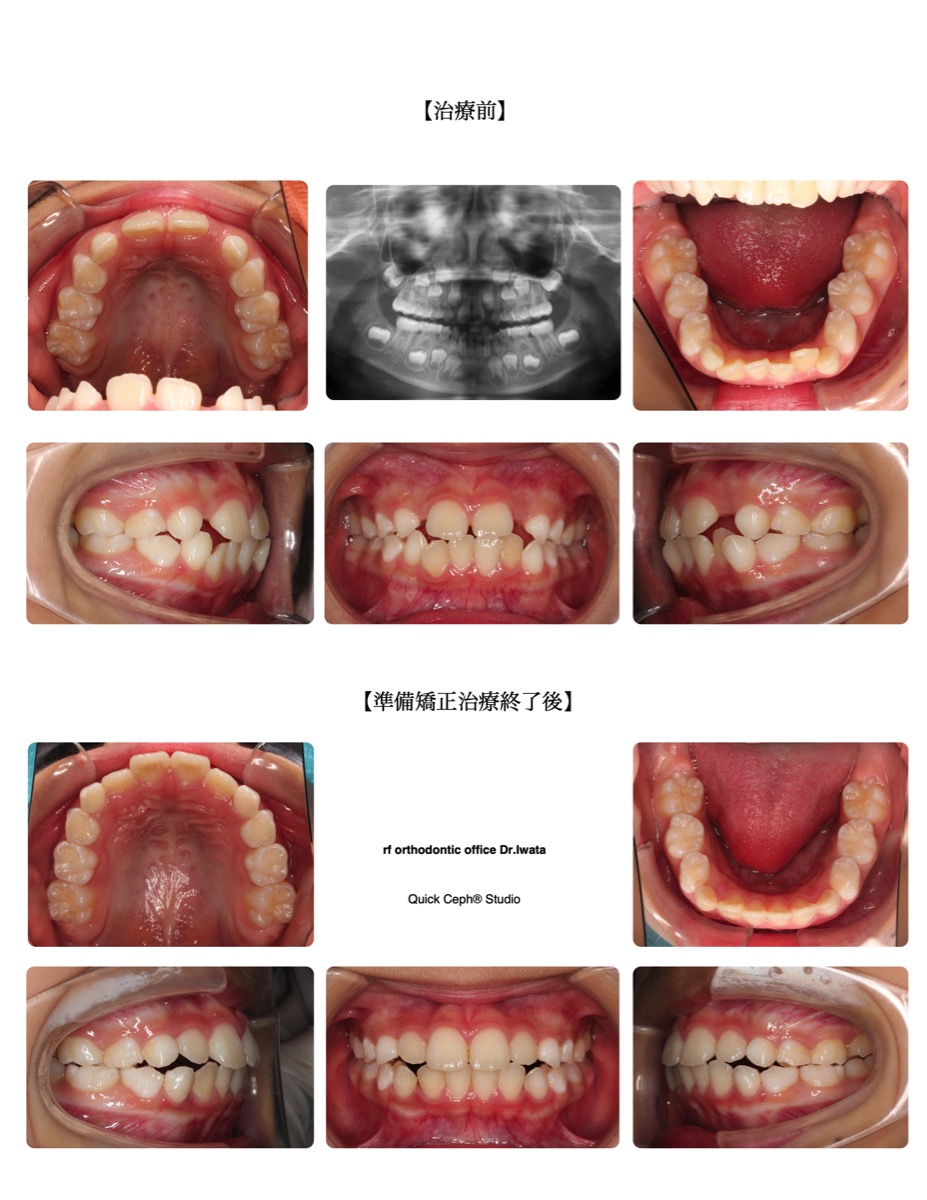

case1

叢生(でこぼこ)

歯が一列に並びきらず、デコボコになっている噛み合わせ。